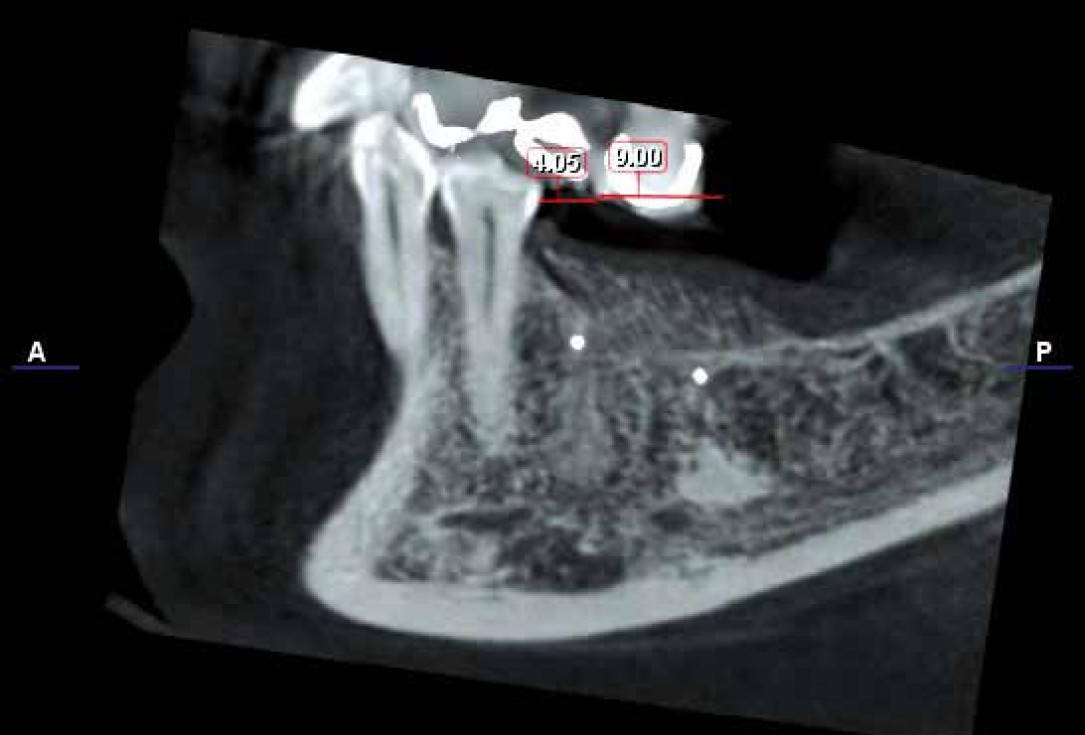

Regeneration of a 9 mm vertical bone defect with cerabone®, autologous bone and S-PRF –  Dr. A. Eslava